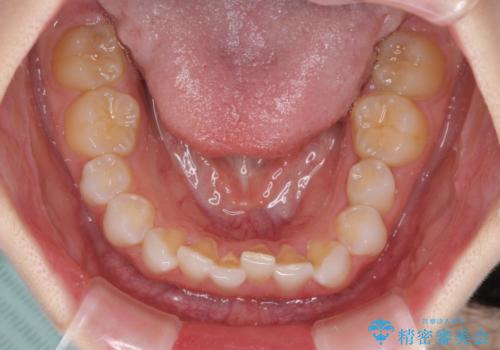

デコボコと深い咬み合わせの改善 インビザラインによる矯正治療

- 口元のデコボコと深い咬み合わせ(ディープバイト)を気にして来院された患者様です。

インビザラインによる上下歯列の拡大と、IPR(歯と歯の間を削る)にるスペースの獲得により、口元のデコボコとディープバイトを改善することとしました。